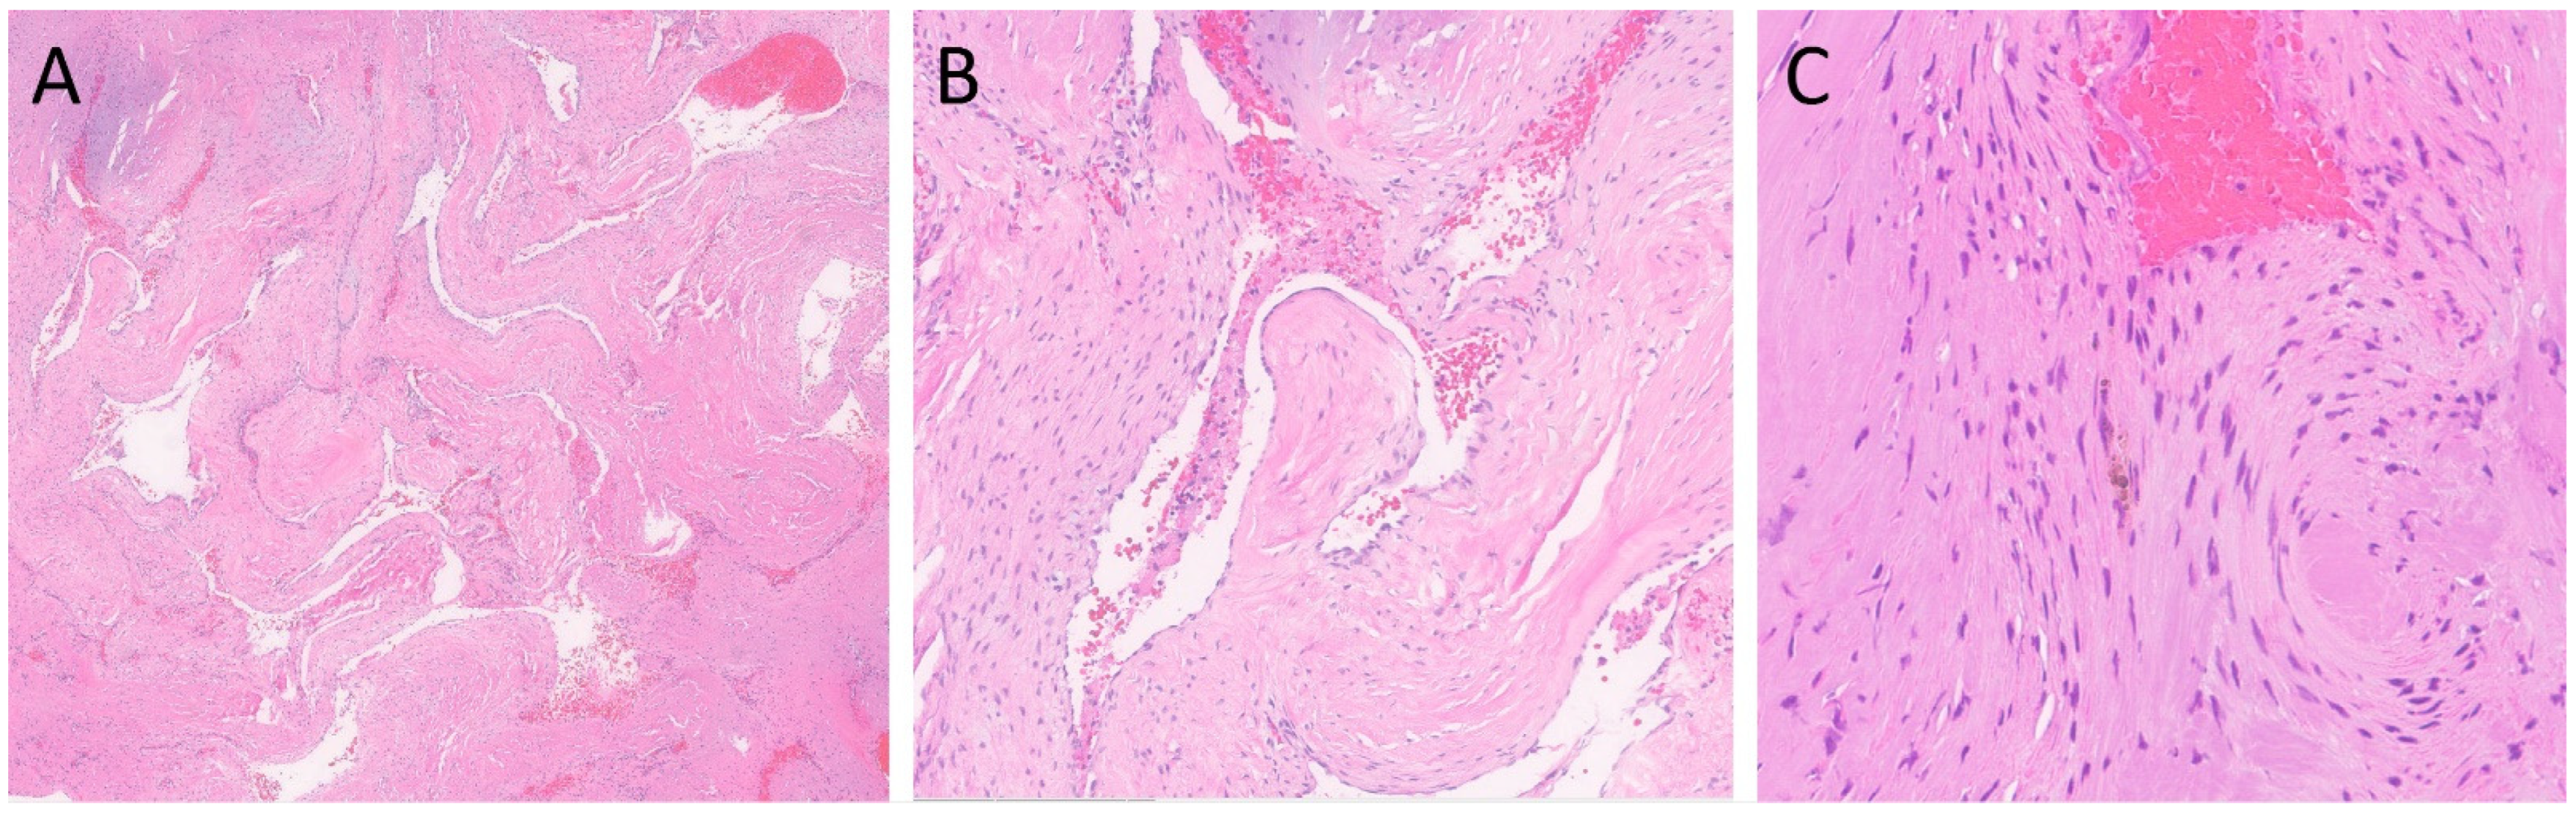

2. Case Presentation